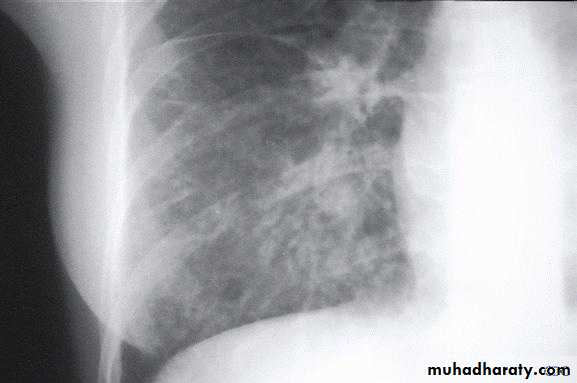

Chest radiograph may show reticulonodular or interstitial infiltration, primarily in the lower lobes.

Clinical-radiographic dissociation is seen often in patients with Mycoplasma pneumoniae or viral pneumonia.